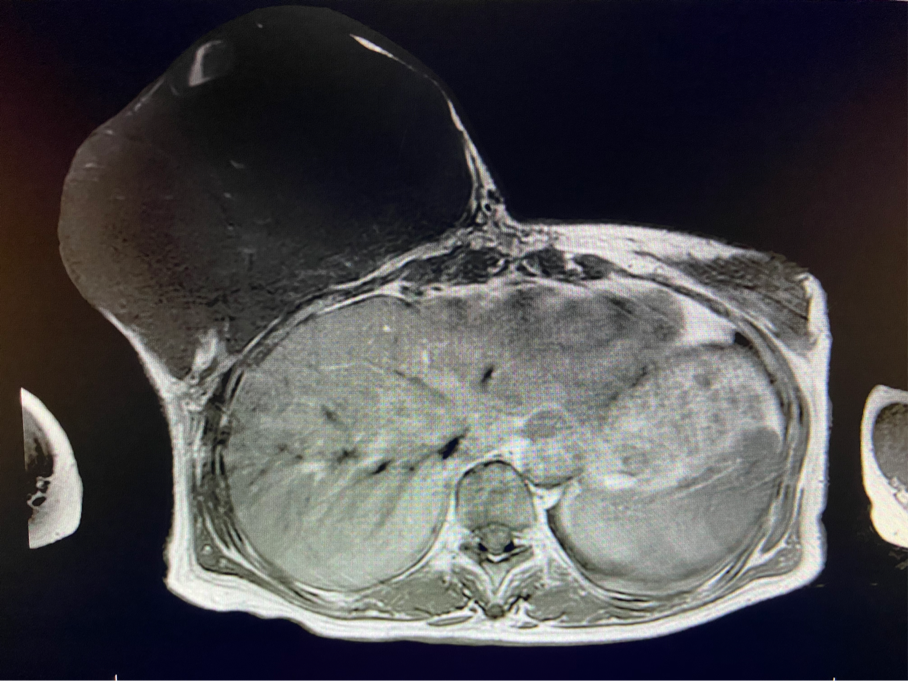

6個(gè)月前,王女士能感覺到右乳腫物明顯增大至“鴨蛋”一般,而且伴有局部皮膚瘙癢及輕度脹痛,可這次王女士并沒有那么幸運(yùn),服藥3個(gè)月不僅沒有控制住腫物,脹痛也越發(fā)嚴(yán)重,超聲檢查提示:右乳囊實(shí)性占位,最大前后徑約10.8cm,右腋窩多發(fā)腫大淋巴結(jié),遂行右乳腫物穿刺活檢術(shù),術(shù)后病理檢查提示:右乳腫物穿刺乳腺組織2條,均可見導(dǎo)管囊性擴(kuò)張,部分區(qū)域間質(zhì)纖維增生,其中1條內(nèi)導(dǎo)管上皮成普通型增生。輾轉(zhuǎn)當(dāng)?shù)囟嗉裔t(yī)院藥物治療后,錢沒有少花,但是療效甚微。

2周前,王女士的右乳外下方皮膚破潰,伴大量滲液,還發(fā)出陣陣惡臭。經(jīng)多方打聽,王女士從外地來到西安國際醫(yī)學(xué)中心醫(yī)院甲乳外科劉曉敏主任處就診。入院后,迅速完善了一系列相關(guān)術(shù)前檢查:王女士的雙乳外形不對(duì)稱,右乳約22?20cm,皮膚水腫明顯并可見靜脈曲張。右乳外下象限皮膚可見局部破潰,創(chuàng)面有3處,共約6?4cm大小,創(chuàng)面呈暗紅色,伴有血性滲出及惡臭,局部皮膚溫度升高。右側(cè)腋窩可觸及腫大淋巴結(jié)。

該患者右乳巨大腫物術(shù)前初步考慮乳腺葉狀腫瘤可能,因腫瘤太大,幾乎遍及整個(gè)右側(cè)乳房,為保證“無瘤原則”,術(shù)中切除范圍位置未知,極有可能出現(xiàn)皮瓣缺損。于是,經(jīng)過和整形醫(yī)院郭樹忠院長、整形外科王愛武主任的討論,提供了兩種手術(shù)方式,一是創(chuàng)面修復(fù)(植皮或轉(zhuǎn)移皮瓣修復(fù)創(chuàng)面),二是乳房再造,與患者及家屬溝通后,決定先解決腫物,3年病情不再復(fù)發(fā)后,可以再考慮乳房重建。